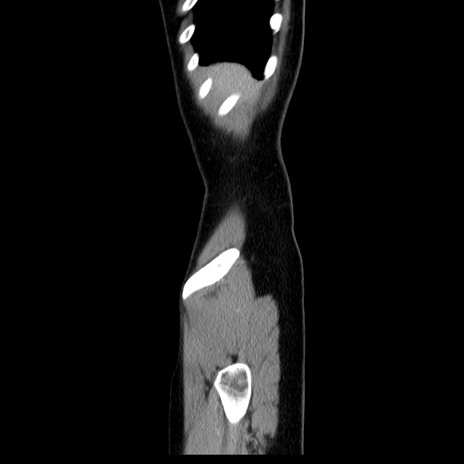

症例39(矢状断像)

【症例】40歳代女性

【主訴】上下腹部痛

【現病歴】2日目から下腹部痛あり。夜間は痛みで眠れなかった。昨日より上腹部痛と下痢が出現。臥位で痛みは軽快したため、休んでいた。本日になって臥位でも立位でも痛みが強くなってきたため救急要請。

【既往歴】子宮内膜症

【身体所見】部:平坦・軟、左上下腹部に圧痛あり、反跳痛あり。

【データ】WBC 21800、CRP 26.78

CT